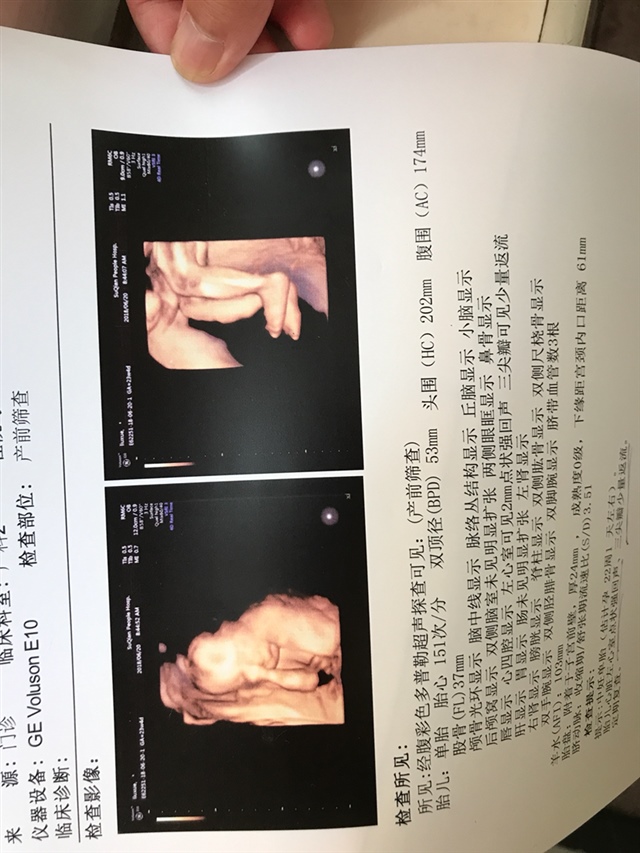

产前检查 B超